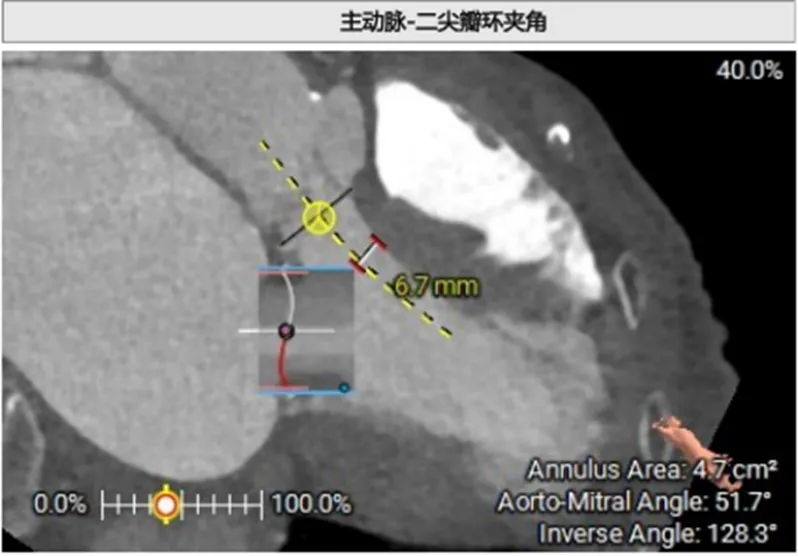

由于二尖瓣环和主动脉瓣角度过大,若采取经心尖方式,同轴性不佳,且难以调整定位件,同样采取经房间隔方式。

1.二尖瓣环与主动脉环平面夹角= 128.3°>105°

2.瓣膜与室间隔最短距离= 6.7mm>6mm